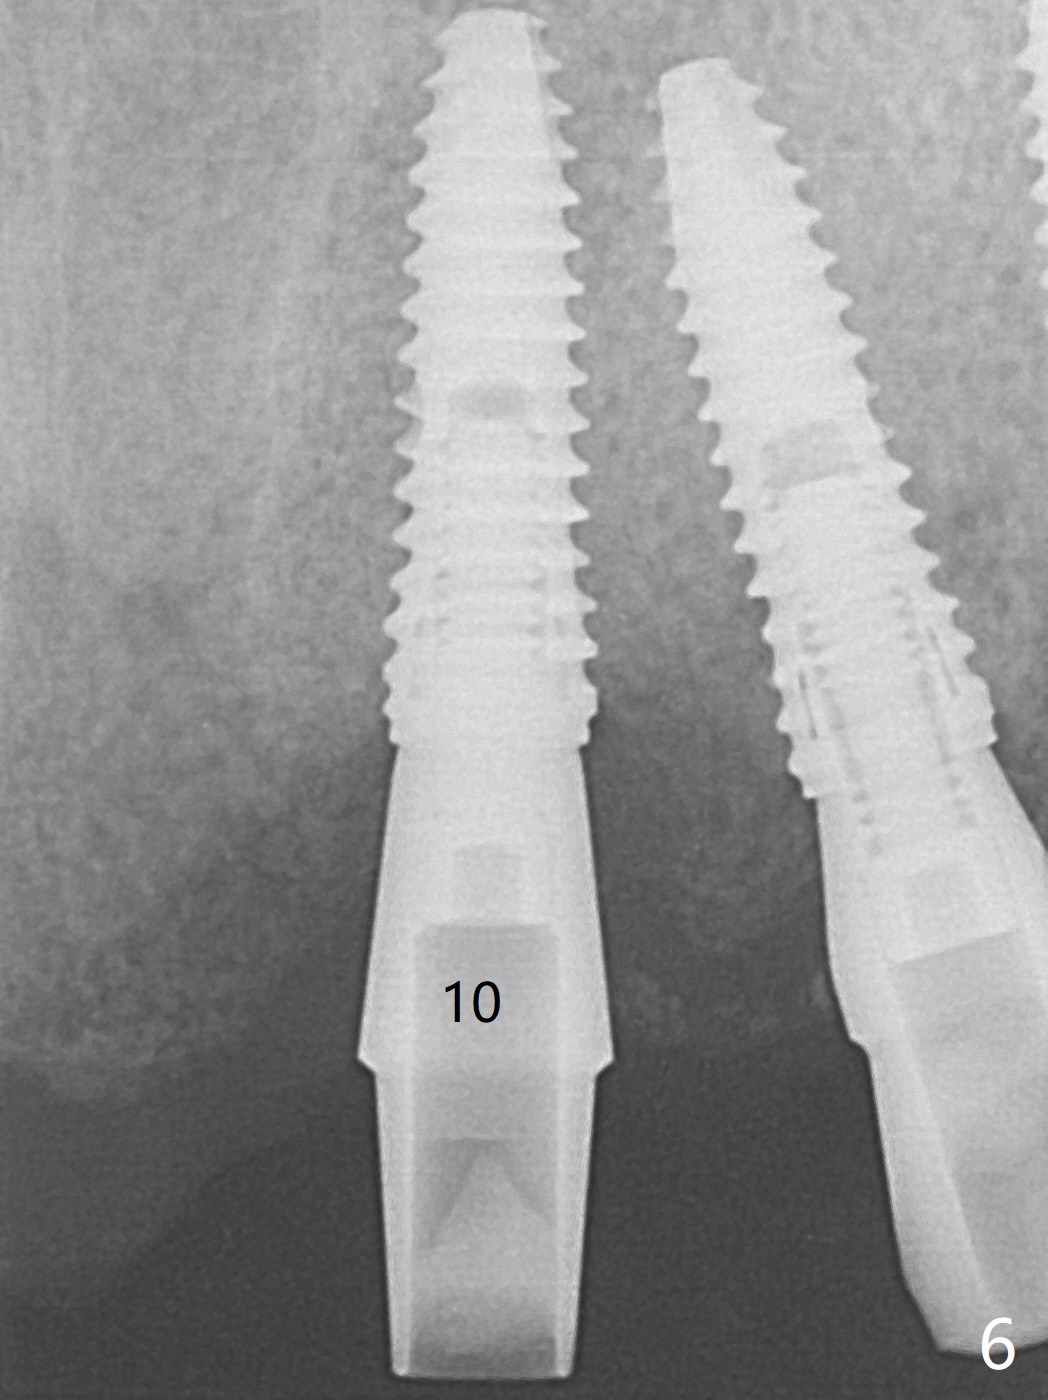

With temporarization of #3,4,13-15 (Fig.1), the anterior clearance is maintained (Fig.2). When provisional is removed, there is no papilla between #7 and 8 (Fig.3,4). After confirmation of complete seating of the abutments at #6 and 10 (Fig.5,6), gingivectomy is conducted with Diode laser (Fig.7,8). Following provisional being relined and modified, the anterior papillae form (Fig.9).